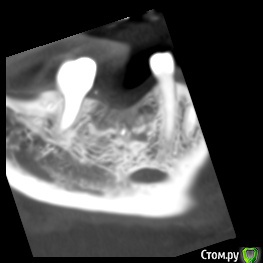

dentikl Опубликовано 26 ноября, 2019 Поделиться Опубликовано 26 ноября, 2019 В августе планировали имплантацию отсутсвующего 46 .Сделали кт,почистили .3 месяца. Ждать или уже ставить? Ссылка на комментарий

Irouil Опубликовано 26 ноября, 2019 Поделиться Опубликовано 26 ноября, 2019 Ставить 2 Ссылка на комментарий

red_butler Опубликовано 26 ноября, 2019 Поделиться Опубликовано 26 ноября, 2019 +1 ставить 1 Ссылка на комментарий